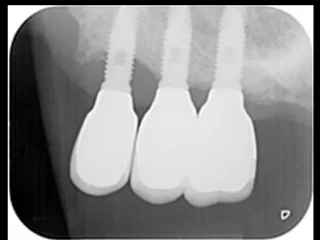

CASE No.4 大月 基弘 先生(大阪府大阪市開業)

施 術 前 (レントゲン写真)

Labrida 施 術 後(2週後 )

PPD7㎜からPPD3㎜、

BOP(ー)に変化、炎症消失